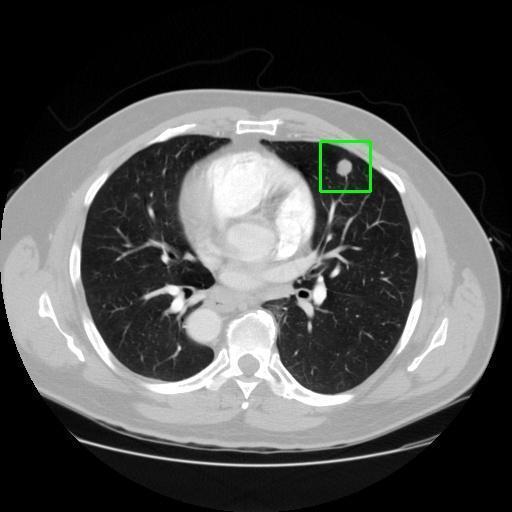

We developed an AI-based system using deep learning models for analyzing lung CT scans to detect and classify pulmonary nodules. We chose the YOLOv11 architecture for its enhanced object detection capability and adapted it specifically for medical imaging, incorporating pixel-level precision and severity classification.

Classification into three severity levels with colored bounding boxes.

Designed a severity classification system that categorizes nodules into null, moderate, and severe using colored bounding boxes, assisting in rapid clinical decision-making.